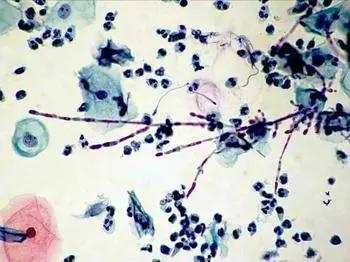

形态学转换显示能力白色念珠菌获得丝状和酵母形式。丝状菌丝以菌丝或假菌丝两种形式存在。两种形式的变化都是由生态因素引起的,例如pH值、温度和氨基酸的存在。体内研究表明,野生型菌株的感染比丝状或酵母形式更致命,死亡率最高。酵母形式易于组织和细胞粘附。在人体细胞中,假菌丝会增强破坏力并削弱免疫系统。另一项研究表明,这两种菌丝形式白色念珠菌是有毒力的,与菌丝形式相比,假菌丝形式的毒性较低,更容易从组织中清除。

菌丝形成是毒力和渗透的重要步骤C.白色念珠菌。几乎没有菌丝作用入侵的证据,而酵母形式与定植有关。但菌丝在颊上皮中形成重要的定殖者,因此菌丝形成不是表皮入侵的必要步骤。体外实验表明菌丝具有触变性等特性。的组织病理学研究白色念珠菌感染组织,菌丝分布不均。